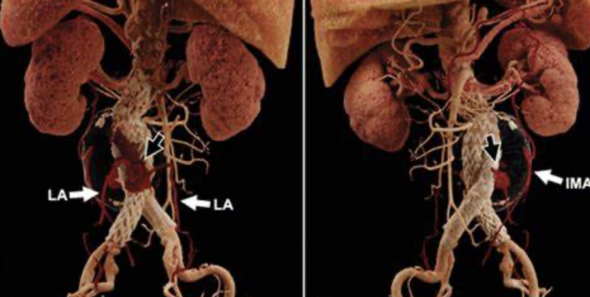

Type II: collateral vessel

IIa: IMA

IIb: Other Branches

II型内漏的原因

肠系膜下动脉(IMA)>3mm、腰动脉>2mm

IMA ≥3 mm in diameter

lumbar arteries ≥2 mm in diameter

an aortoiliac-type aneurysm